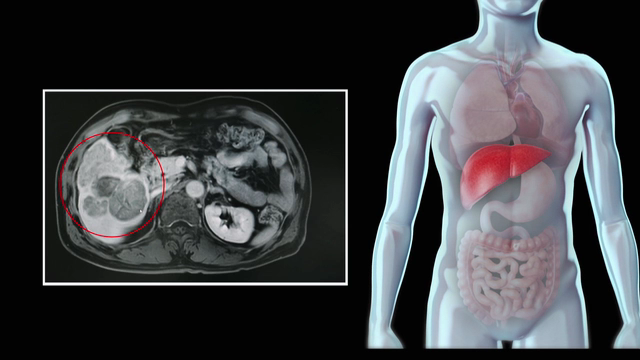

간질환 완치에 도전하는 명의들을 만나 발전하는 치료법을 소개한다. 말기 간질환 환자들의 유일한 희망은 간이식이다. 이제는 혈액형이 다르더라도 혈장교환술을 이용한 혈액형 부적합 간이식이 가능해졌고 간이식 생존율도 꾸준히 향상됐다. 간이식으로 두 번째 삶을 선물받은 사람들을 만난다.

지난해 '알프스'라 불리는 최신 간암 수술법이 소개됐다. 암을 부분적으로 절제한 후 남아 있게 될 간을 충분히 키우고, 최종적으로 암을 잘라내는 고난도 기술이다. 재생이 잘 된다는 간의 특성에 집중해 고안된 수술법이다.

최근에는 간염 바이러스 때문에 딱딱해졌던 간이 서서히 재생되어 간 기능을 회복할 수 있게 됐다. 어떤 치료 방법으로 간염 바이러스를 잡았을까? 소화기내과 전문의 임영석 교수와 함께 간염 치료의 현주소를 살펴보고, 간염을 이겨낸 사람들의 이야기를 들어본다.